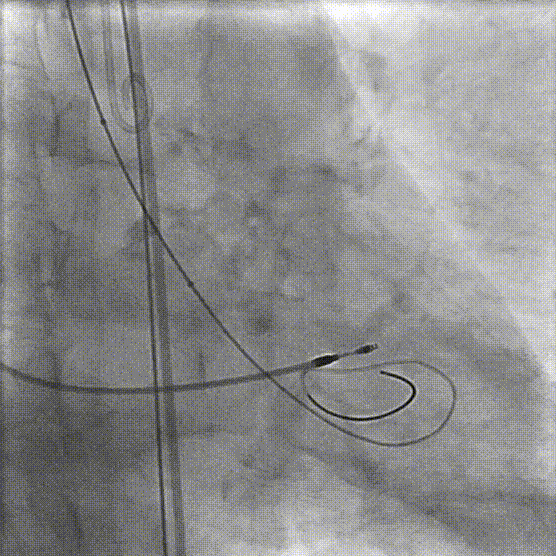

复查下肢造影显示右髂总动脉-右股总动脉明显狭窄

更换V18导丝后再次送入6.5×60mm赛禾外周冲击波球囊,充盈至4atm下进行一个周期的脉冲治疗

复查右侧髂总动脉-股总动脉造影较前狭窄明显减轻